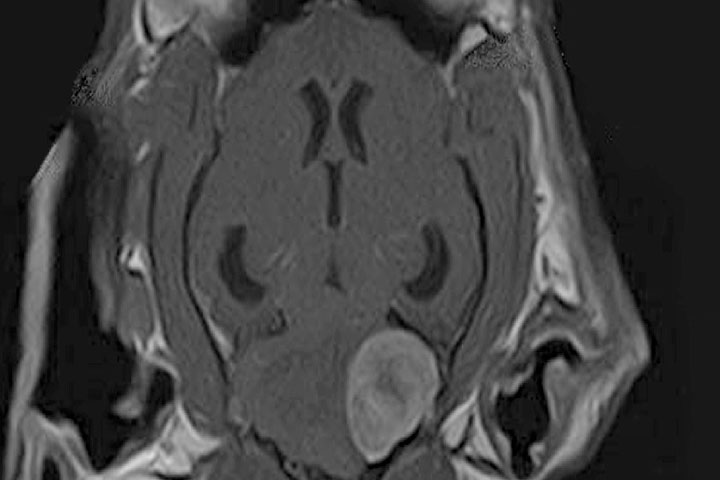

Gliomas

Gliomas are the second most common primary brain tumour in dogs. They are more prevalent in brachycephalic breeds, but rare in cats.

On MRI they appear as intra-axial masses with mass effect and heterogeneous contrast uptake. Some can have accompanying signs of haemorrhage (T2* signal void).

Gliomas can be divided histopathologically in oligodendrogliomas and astrocytomas, with different grades of malignancy; from slow growing to highly aggressive glioblastoma multiforme or gliomatosis cerebri.